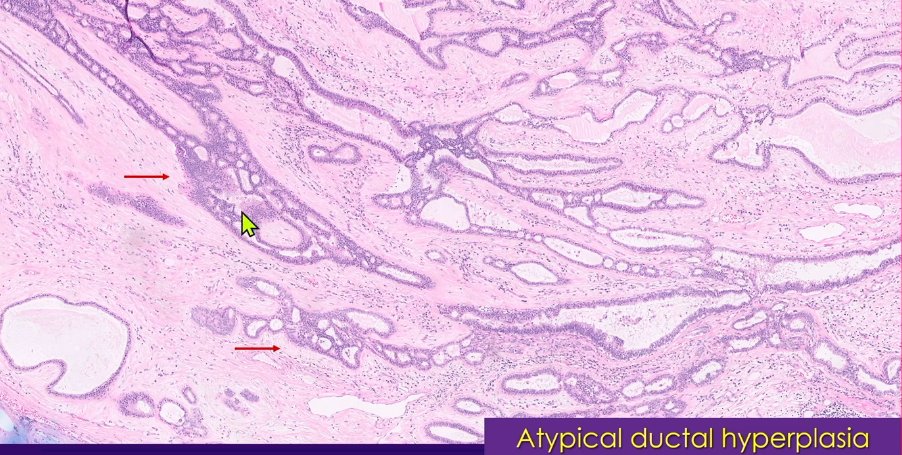

Less common features seen in fibroadenomas - Irregular borders/fat entrapment - Stromal multinucleated cells - Chondroid metaplasia - Pregnancy secretory changes - Columnar cell changes - Atypical ductal hyperplasia - Intraductal papilloma - Sclerosing adenosis - Radial scar -